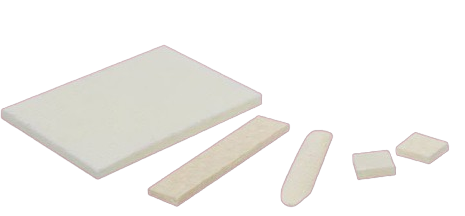

| Mechanical Strength | มีให้เลือกหลายความหนา (3–4 mm) คงความทนทานได้ดีในการทดสอบด้วย collagenase | ปานกลางถึงสูง ขึ้นอยู่กับรุ่น/ความหนา | มักแข็งแรงกว่าเล็กน้อย เหมาะสำหรับการเสริมในช่องปาก/โพรงจมูก |